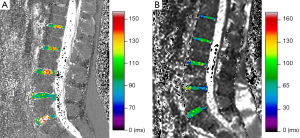

We used MINC tools and Display software (McConell Brain Imaging Center, Montreal, Quebec, Canada) to analyze the images. The relaxometry maps were generated using homemade scripts based on MINC tools from the corresponding data. T1ρ and T2 maps were computed on a pixel-by-pixel basis using an exponential decay model (Figure 1). S0 and S(TSL) are the equilibrium magnetisation signal and T1rho-prepared magnetisation signal with the spin-lock time of TSL. S(TE) is the signal acquired with the echo time (TE):

Five lumbar IVDs were manually segmented to the full extent, i.e., encompassing the complete NP and AF, considering all sagittal slices and taking care not to segment the subchondral bone and vertebral endplate, in the last echo image (TE =160 ms) of the T2 multiecho acquisition (Figure 2A).

Another segmentation was performed using only the central sagittal slice of each lumbar MRI using regions of interest (ROIs) of fixed dimensions (26.77 mm2) and positioned at the NP, anterior annulus fibrosus (AAF) and posterior annulus fibrosus (PAF) (Figure 2B). Our ROI positioning methodology was similar to the manual approach of Mok et al. (15). The nucleus ROI was placed in the most central area of the disc. The annulus ROI were positioned in the most anterior and posterior portions of the disc. A clear separation of NP and inner AF was not possible especially for degenerated discs. The endplates and ligaments would all appear as dark signals on T2-weighted images, therefore, sufficient space was allowed for dark signal band near the endplate, near the anterior border close to the abdominal fat, and near the posterior border close to the spinal fluid.

After the volumetric segmentation, the IVD volumes were obtained from the disc labels. These labels were superimposed in the relaxometry maps to extract T1ρ and T2 values (Figure 3).